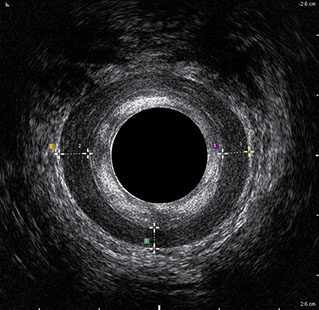

L’ecografia transanale è un esame diagnostico per immagini che consiste nell’introduzione di un trasduttore ad ultrasuoni. Le immagini qualitativamente migliori del canale anale sono ottenute usando un trasduttore rotante, montato in un manipolo rigido, che fornisce un’immagine a 360°. Con le apparecchiature più moderne è anche possibile ottenere immagini tridimensionali.

L’ecografia transanale permette di distinguere la sottomucosa che riveste il canale anale, lo sfintere anale interno, e lo sfintere anale esterno.

Le principali indicazioni all’esecuzione di tale esame sono lo studio dell’integrità delle strutture muscolari nei casi di incontinenza fecale, lo studio topografico dei processi settici perianali (ascessi e fistole) e lo studio dei processi proliferativi epiteliali (carcinoma anale).

Proctal dispone di apparecchiatura per ecografia endoanale 3D con sonda rotante.